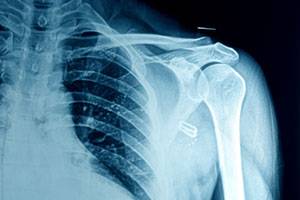

Перелом хирургической шейки со смещением и без

В тяжелых случаях, его видно сразу, потому что отломки проступают под кожей. Переломы сопровождаются болью, при медленном движении слышен хруст. Обычная активность руки невозможна.

Одним из главных признаков будет кровоизлияние по передней поверхности плеча и ряд других симптомов: отек, нарушение подвижности, болезненность при пальпации. Ось плеча не нарушена.

При попадании пациента в лечебное учреждение, снимают болевой синдром и делают рентген. Для уточнения характера травмы назначают компьютерную томографию и МРТ.

При переломах со смещением назначают репозицию (т.е. Вправление). Здесь обязательна анестезия. Хирургическое вмешательство показано в более сложных случаях и проводят его под наркозом.

Операция обязательна при установке головки и для фиксации отломков с помощью штифтов или других приспособлений. Снимают фиксирующие устройства через несколько месяцев, если подтверждается срастание.